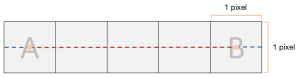

Two commercially available anthropomorphic lung phantoms (LSCT001 and Lungman, Kyoto Kagaku, Japan) were used (Figure 2). LSCT001 is a lung cancer screening phantom; for which, the chest wall and mediastinum consist of a substance radiologically equivalent to water, and the vertebrae and ribs consist of a substance radiologically equivalent to bone. The targeted computed tomography (CT) value of the lung parenchyma is −900 HU. Five types of nodules (diameter: 4, 6, 8, 10, and 12 mm) with 270 HU contrast to the background were embedded in the right lung at three levels: apices, bifurcation, and base of the lungs. Another five types of nodules (diameter: 2, 4, 6, 8, and 10 mm) with 100 HU contrast to the background were embedded in the left lung at the same levels. We used a 10-mm nodule with a 270 HU contrast to the background as the target nodule. The Lungman is a multipurpose chest phantom that consists of simulated pulmonary vessels, heart, trachea, chest wall, diaphragm, and abdomen block. Simulated pulmonary nodules of various diameters and attenuations (diameter: 5, 8, 10, and 12 mm; attenuation: +100, −630, and −800 HU for each diameter) were manually placed within foam inserts to avoid any vessel attachment. We used nodules of 100 HU as the target.

For nodule segmentation, a commercially available software program, LuCAS (Monitor Corporation, Seoul, Korea), was used. LuCAS is a deep learning-based computer-aided diagnosis (DL-CAD) solution that provides detection and segmentation applications for pulmonary nodules. After loading the DICOM images into the software, the software detected nodules and initiated the segmentation (Figure 3). Nodule volume and diameter were quantified in a fully automatic manner.